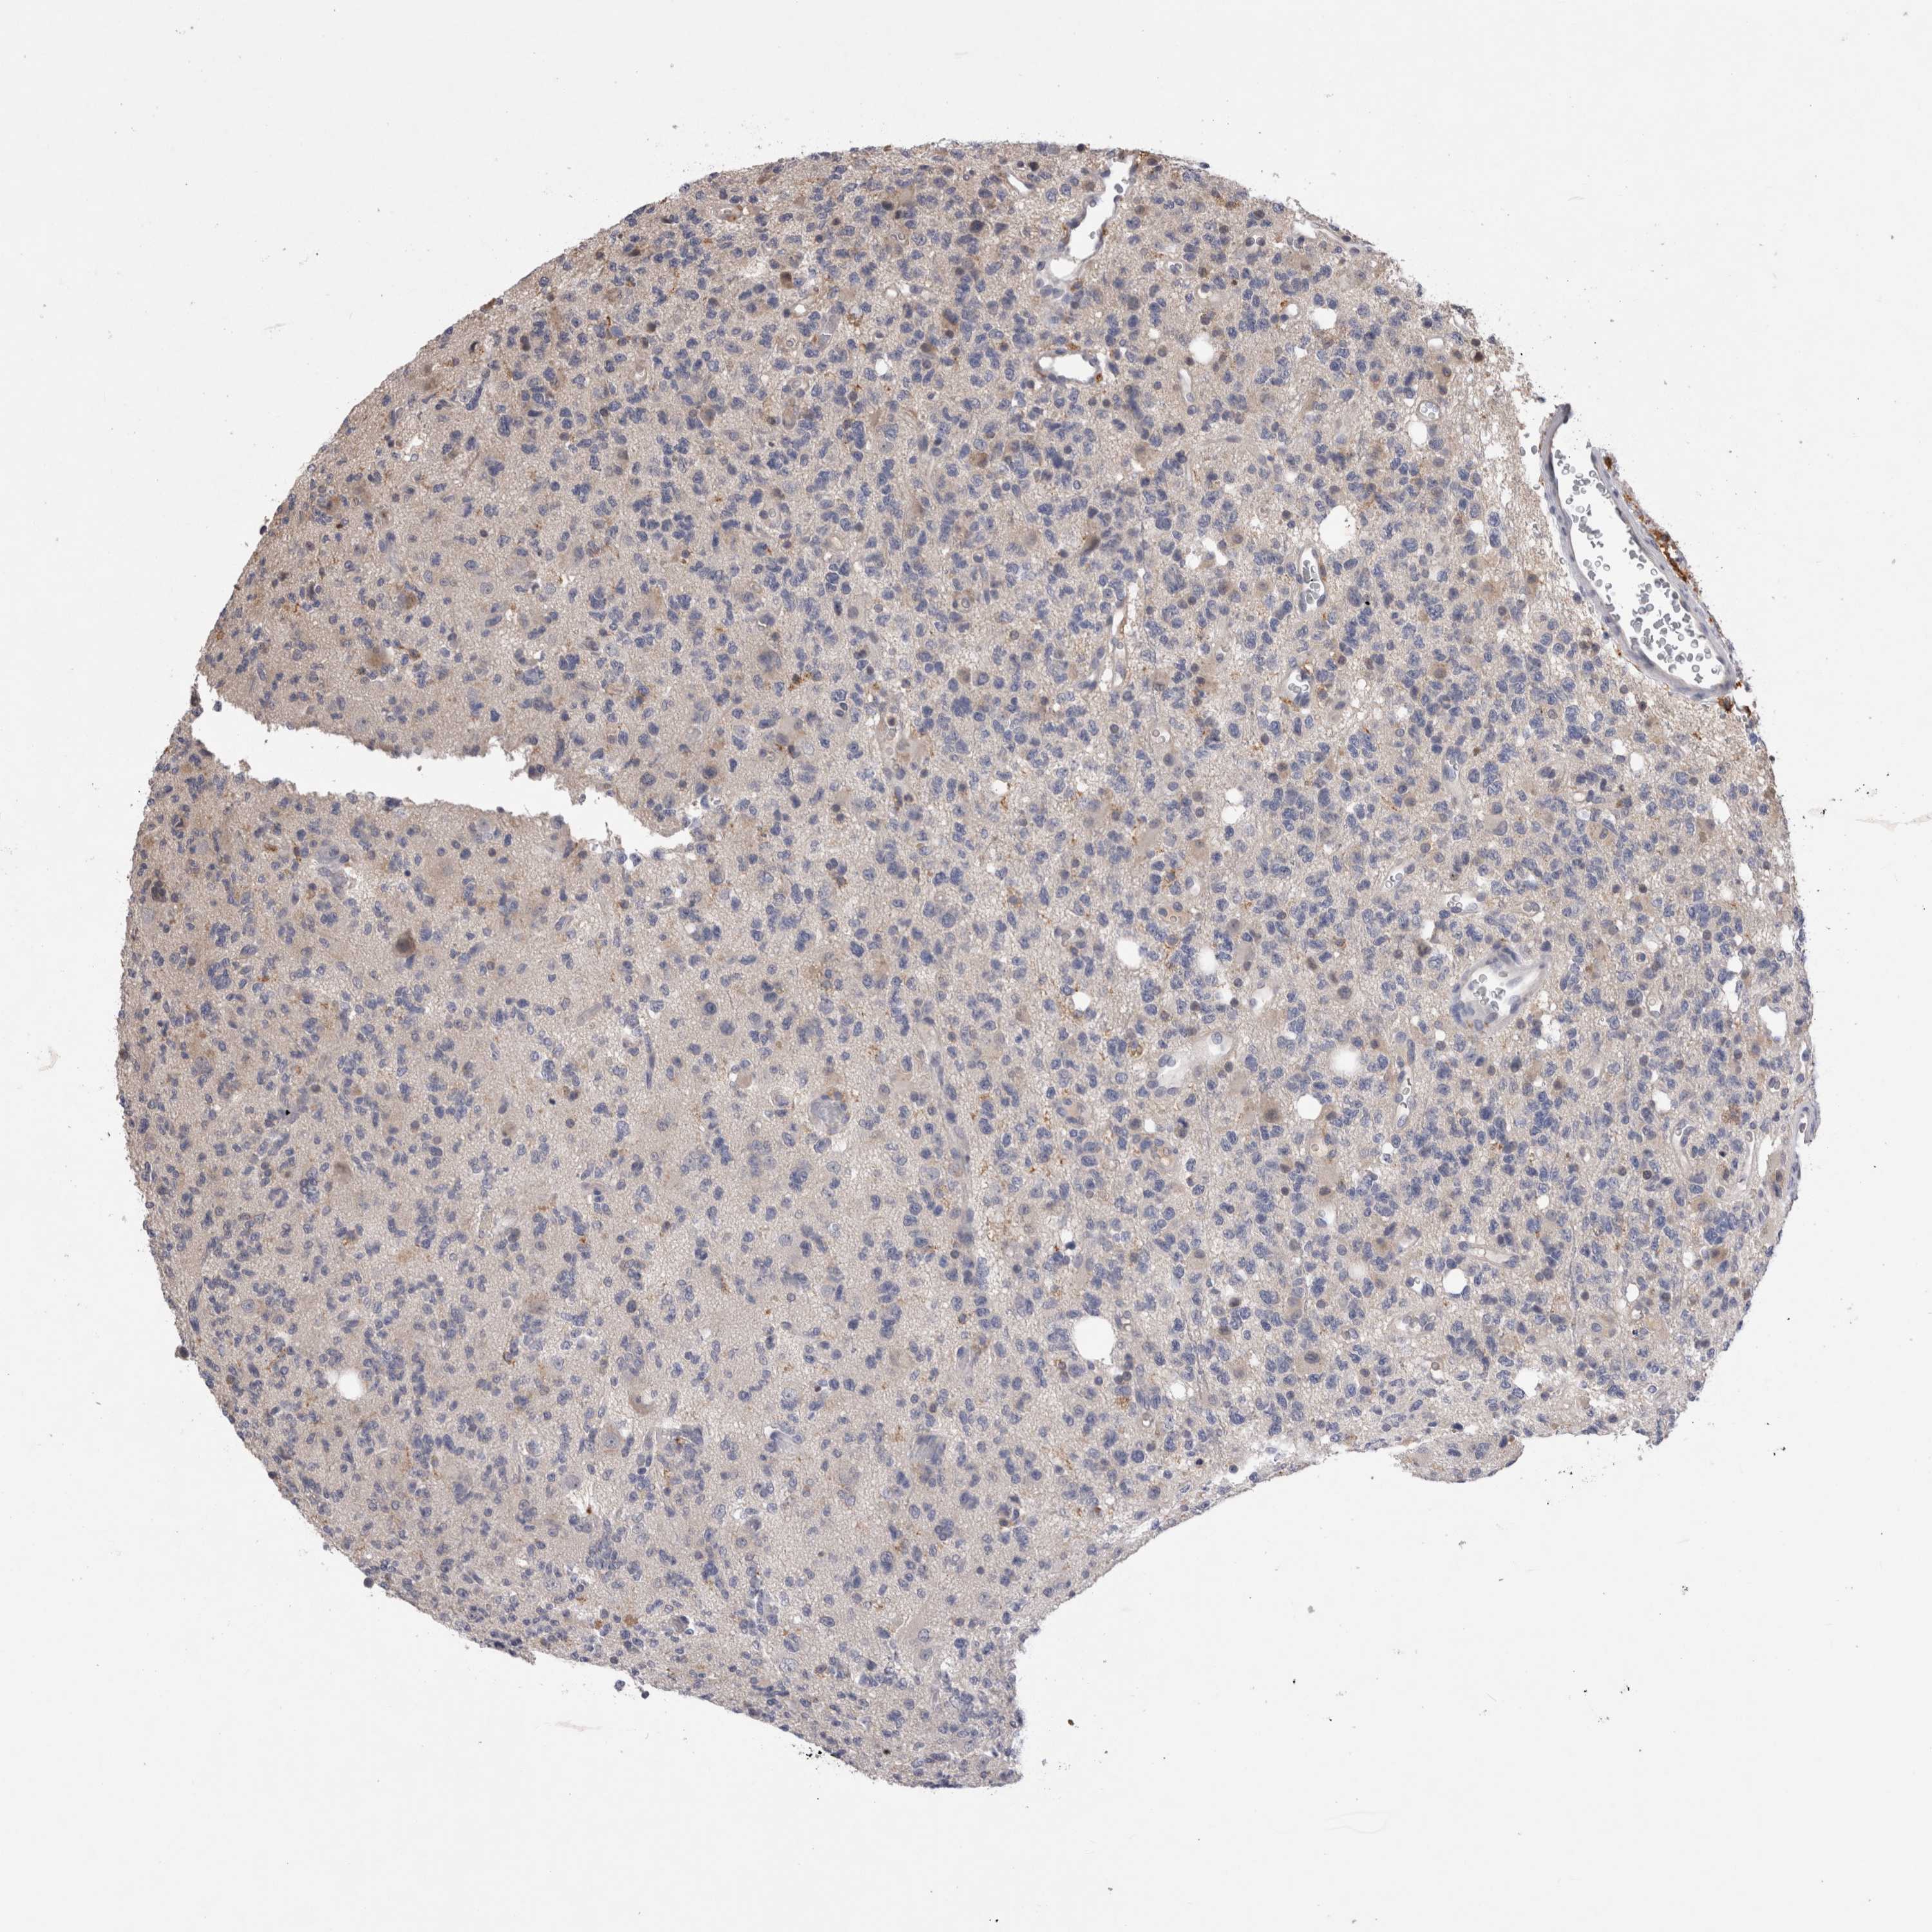

GLIOMA - Protein expressioni

A mouse-over function shows sample information and annotation data. Click on an image to view it in a full screen mode. Samples can be filtered based on level of antibody staining by selecting one or several of the following categories: high, medium, low and not detected. The assay and annotation is described here.

Note that samples used for immunohistochemistry by the Human Protein Atlas do not correspond to samples in the TCGA dataset.

Antibody stainingi

Antibody staining in the annotated cell types in the current human tissue is reported as not detected, low, medium, or high, based on conventional immunohistochemistry profiling in selected tissues. This score is based on the combination of the staining intensity and fraction of stained cells.

Each image is clickable and will lead to virtual microscopy that enables deeper exploration of all samples and also displays staining intensity scores, fraction scores and subcellular localization as well as patient and tissue information for each sample.

Antibody HPA003903

Antibody HPA072756

Antibody CAB026000

Staining

High

Medium

Low

Not detected

Intensity

Strong

Moderate

Weak

Negative

Quantity

>75%

75%-25%

<25%

None

Location

Nuclear

Cytoplasmic/membranous

Cytoplasmic/membranous,nuclear

Glioma, malignant, High grade

Glioma, malignant, NOS

Glioma, malignant, Low grade